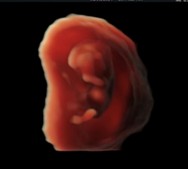

Profile of preborn baby at 10 weeks gestation

This generation has grown up under in a different world of science and technology than the Roe generation. Today’s moms see their babies on ultrasound from the earliest stages of pregnancy. They don’t have to imagine what their babies look like thanks to realistic 3D/4D scans. They know the sex of their babies just weeks into pregnancy through a simple blood test. They follow every step of their baby’s development in a pregnancy app. They understand their pregnancies in ways their grandmothers could have never imagined.